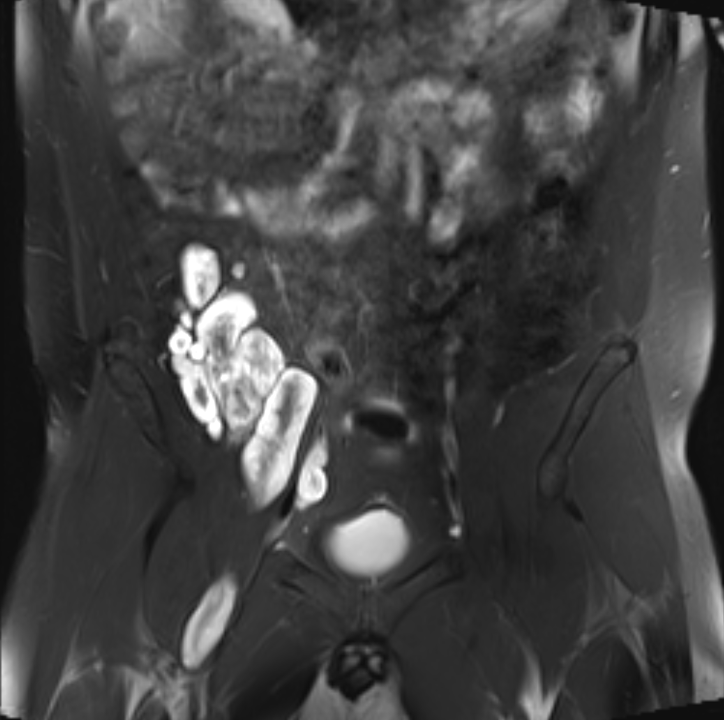

Plexiform neurofibromas Neurofibromatosis Type 1

Multiple neurofibromas Neurofibromatosis Type 1

Target sign

- hypointense centrally

- hyperintense peripherally